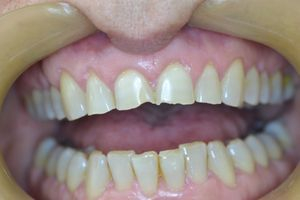

Η νεαρή αυτή ασθενής μας είχε ολοκληρώσει παλαιότερη ορθοδοντική θεραπεία, η οποία είχε οδηγήσει σε νέκρωση τον άνω δεξιό κεντρικό και πλάγιο τομέα.

Τα δόντια αυτά είχαν απονευρωθεί στο παρελθόν και είχαν μαυρίσει.

Τοποθετήθηκαν άξονες υαλονημάτων (ParaPost FiberWhite/Coltene) για ενίσχυση των ριζών και στη συνέχεια χτίστηκαν όψεις ρητίνης (Herculite XVR Ultra/Kerr) για να διορθωθεί η δυσχρωμία τους.